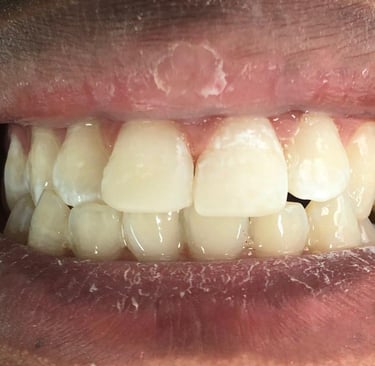

Cirurgia de aumento de coroa clínica antes das coroas

Caso que demonstra a vantagem da integração de diversas áreas da odontologia, unindo cirurgia, periodontia, prótese e estética para alcançar resultados funcionais e harmônicos.

Depois